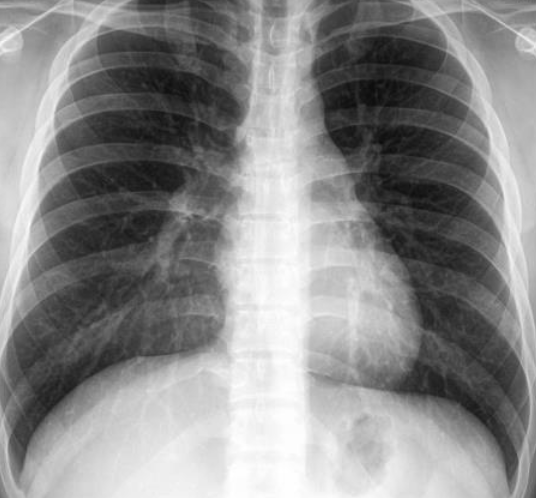

Case 4

Patient with recurrent attacks of dyspnea and chest tightness after exercise. Clinical diagnosis bronchial asthma. Chest X ray is as follows:

Q1: in this chest x-ray normal or abnormal? Normal.

Q2: on chest auscultation, what added sounds can be heard in asthma? Wheeze.

Q3: Name any drug which can precipitate asthma? NSAIDS, Beta blockers.

Q4: You ordered spirometry for this pt. what will be the expected finding? FEV1 is reduced.

Q5: Name 2 clinical features of severe asthma? Z Can Not complete a sentence in one breath, Tachypnea, cyanosis

Q6: What ttt will you give in moderate to severe asthma? Name any 2. Bronchodilators, corticosteroids.